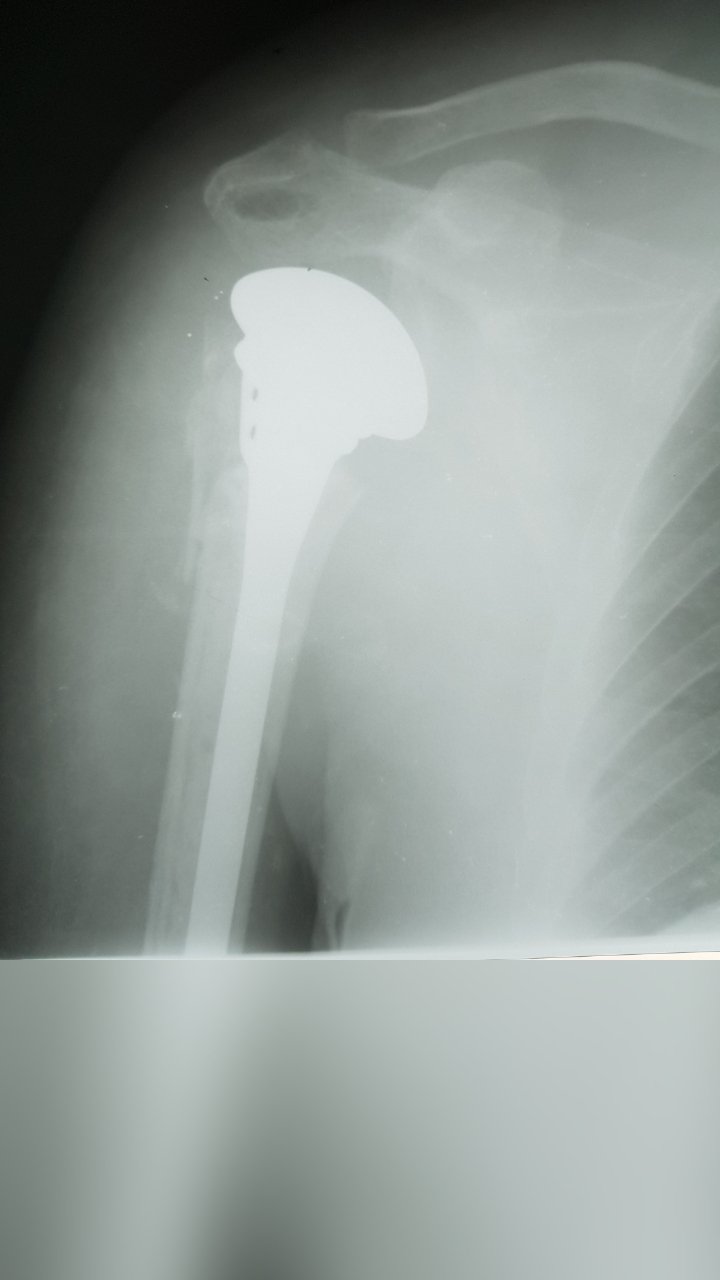

SHOULDER HEMIARTHROPLASTY